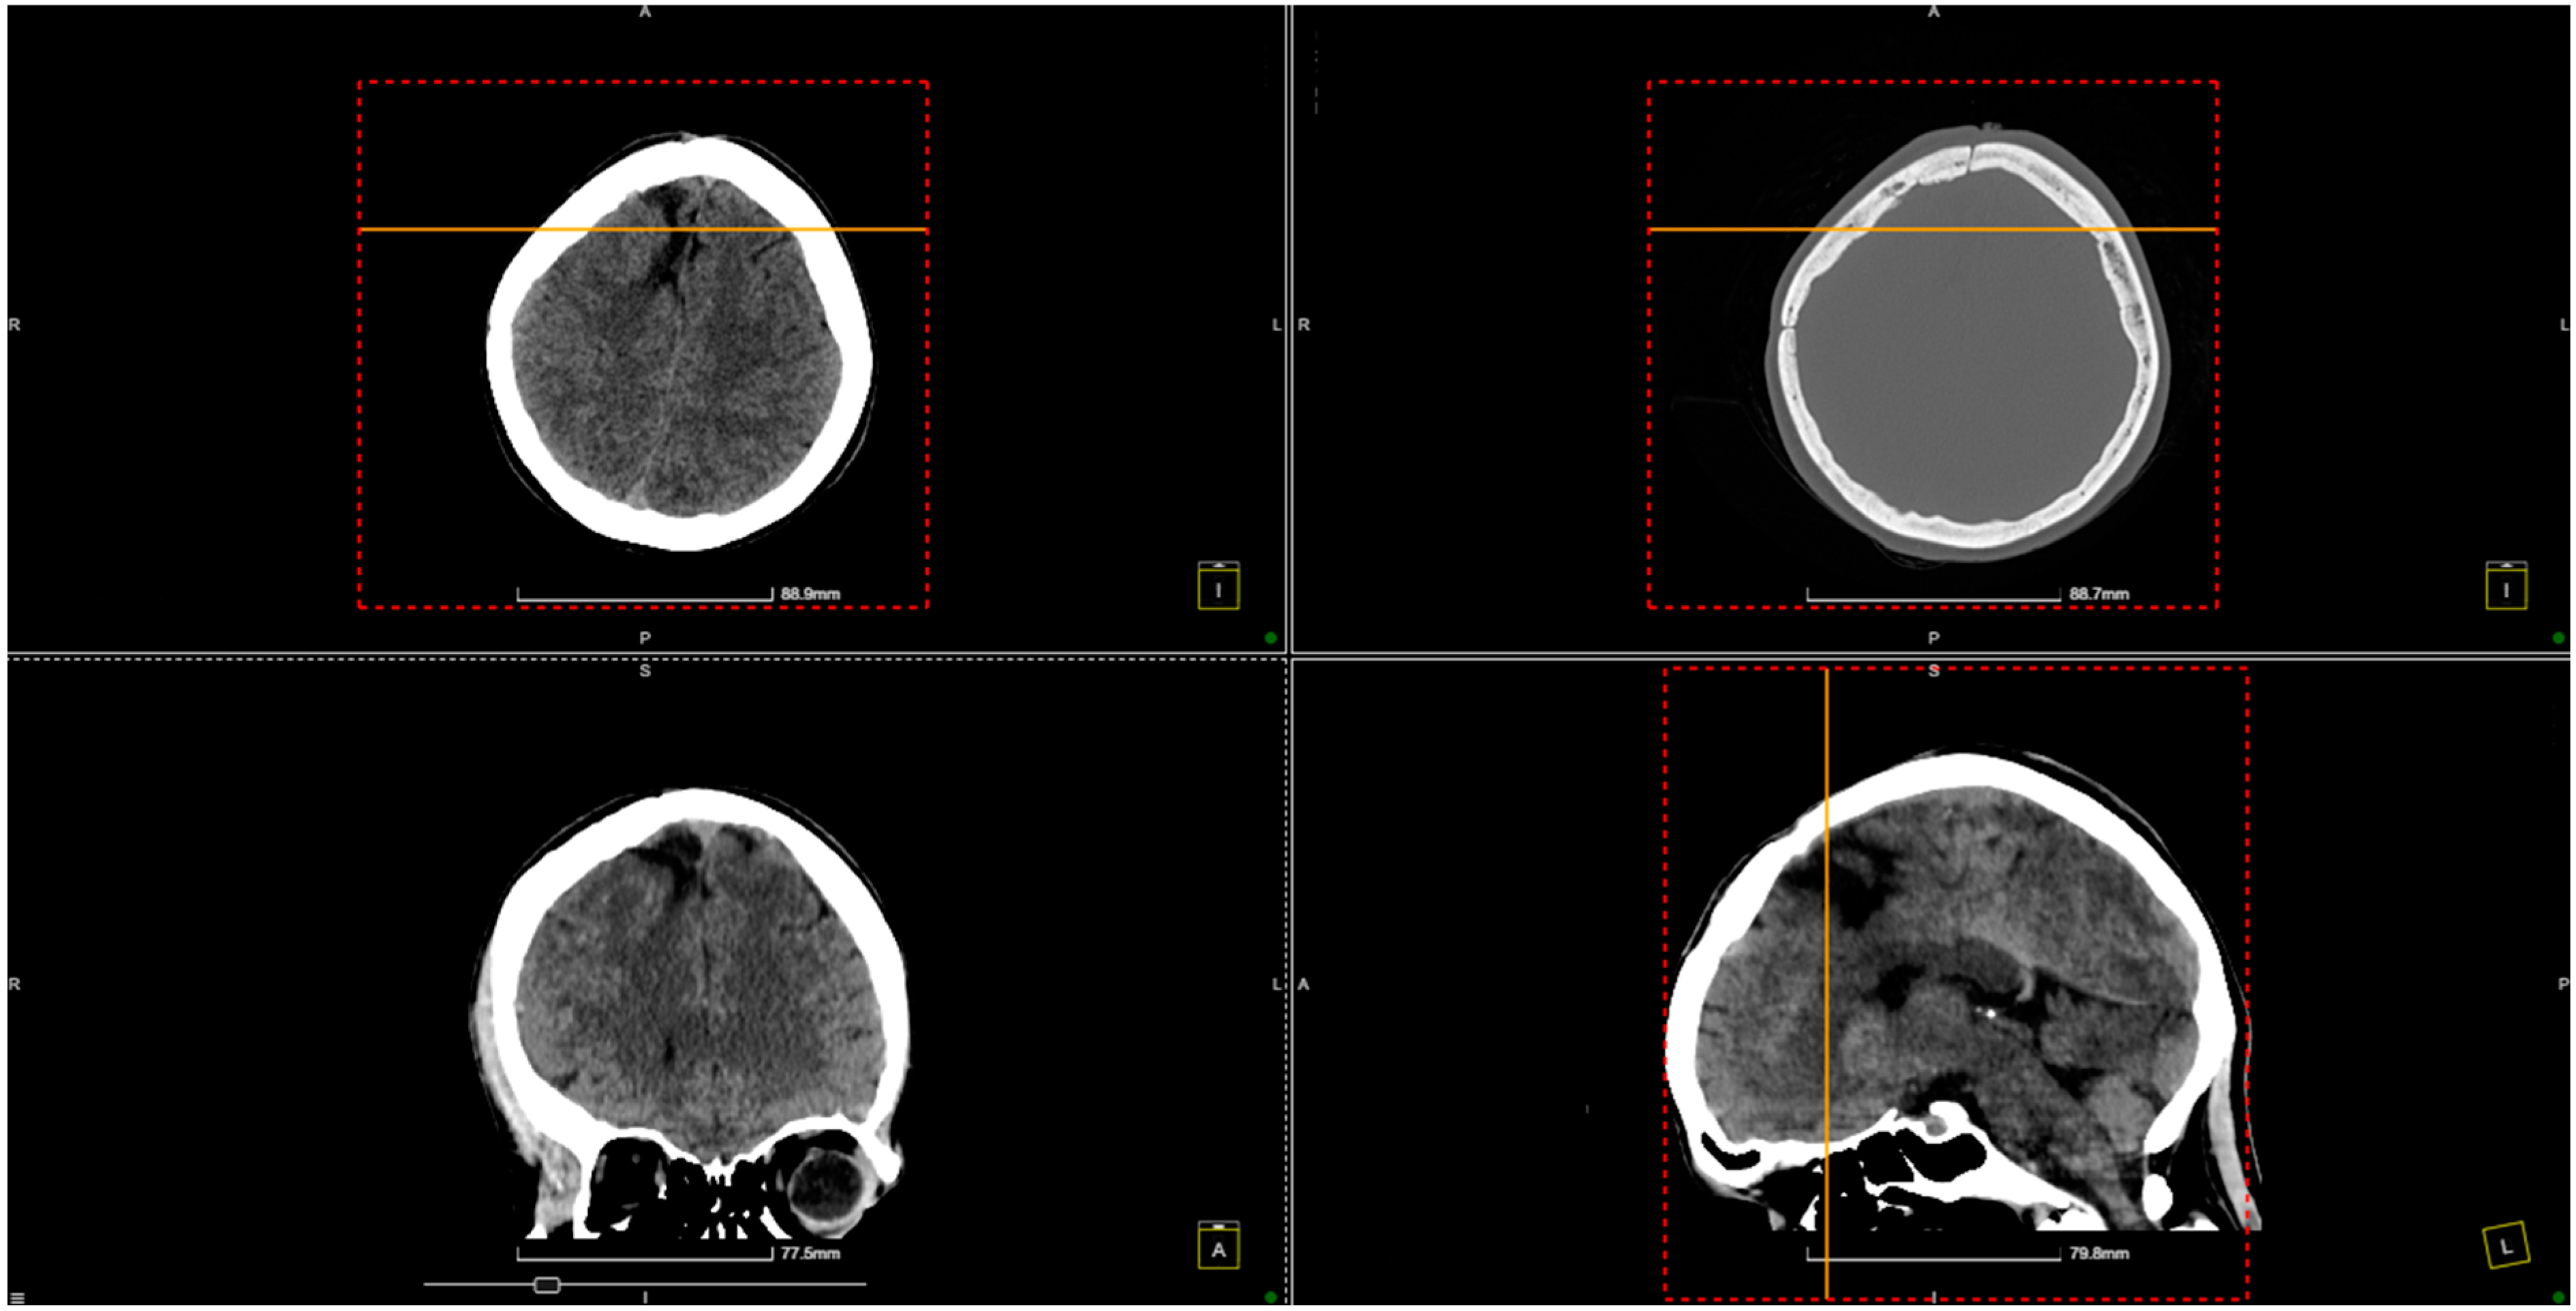

2. Case Presentation